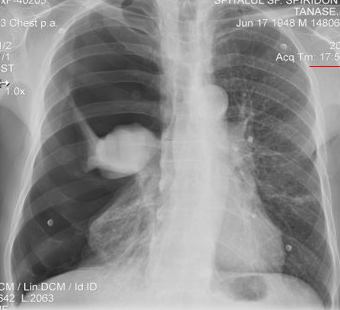

Rx toracică, incidență P-A

DESCRIERE:

DX: emfizem pulmonar

DD: